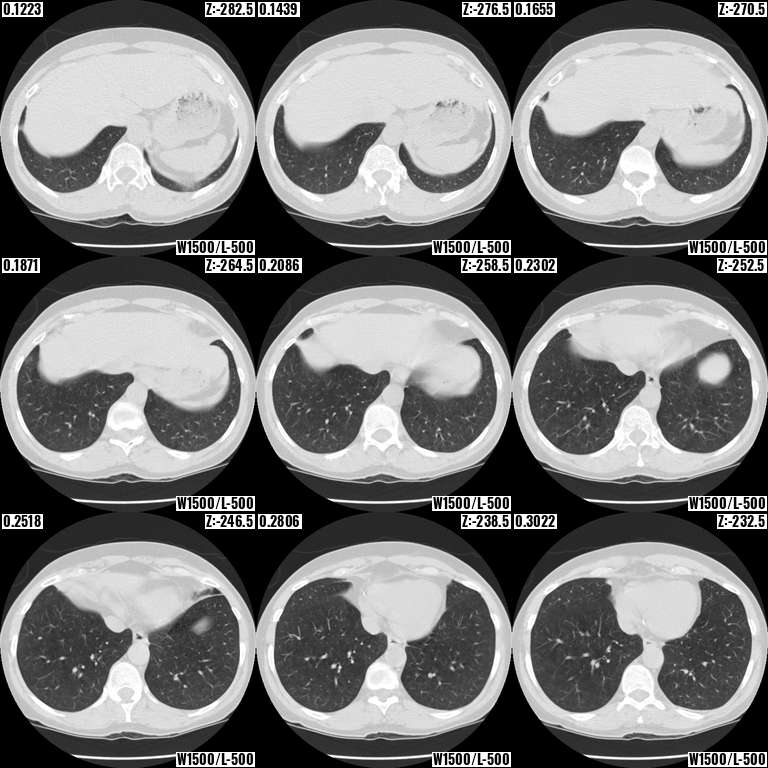

“Find the bottom of the lungs in an IDC NLST series”: